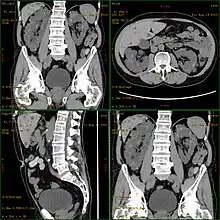

| Severely affected polycystic kidneys removed at time of transplantation | |